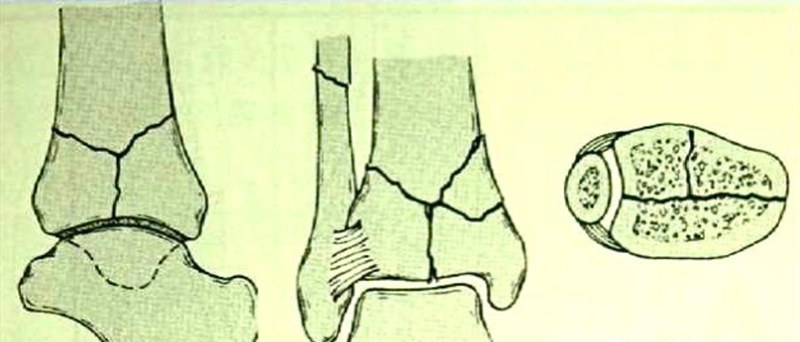

临床常以Ruedi-Allgower分型作为损伤分型。

图3 Ⅰ型:没有移位的踝关节劈裂骨折